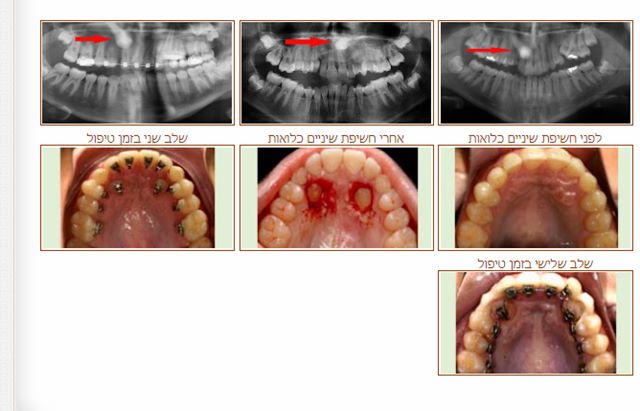

שן כלואה

שיניים כלואות הן שיניים המאחרות לבקוע זמן רב מעל הגיל הממוצע לבקיעתן. הסיכויים לבקיעתם הטבעית של שיניים כלואות הם נמוכים באופן כללי.